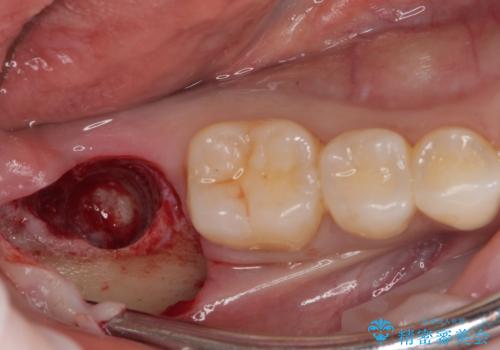

- 奥歯が抜歯となり、インプラント治療を希望して来院された患者様です。

来院時には抜歯して1ヶ月ほど経過していたとのことで、3次元レントゲンよりインプラントの早期埋入が可能と診断されました。

抜歯された骨の穴は、インプラント埋入時にはまだ大きな窩洞となっていましたが、径の大きいワイドインプラントを選択することで、埋入時に十分な安定を獲得することができました。

後方には欠損が残っていたため、補填材を填入しました。